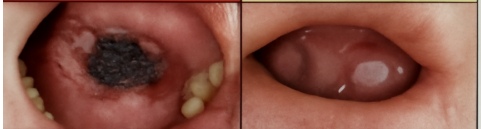

BỆNH SCORBUS – KẺ THÙ THẦM LẶNG TRONG KHOANG MIỆNG

Scorbus là một bệnh lý hiếm nhưng nguy hiểm ảnh hưởng đến mô mềm khoang miệng, đặc biệt là niêm mạc má, lưỡi và vùng dưới lưỡi. Tên gọi “Scorbus”...